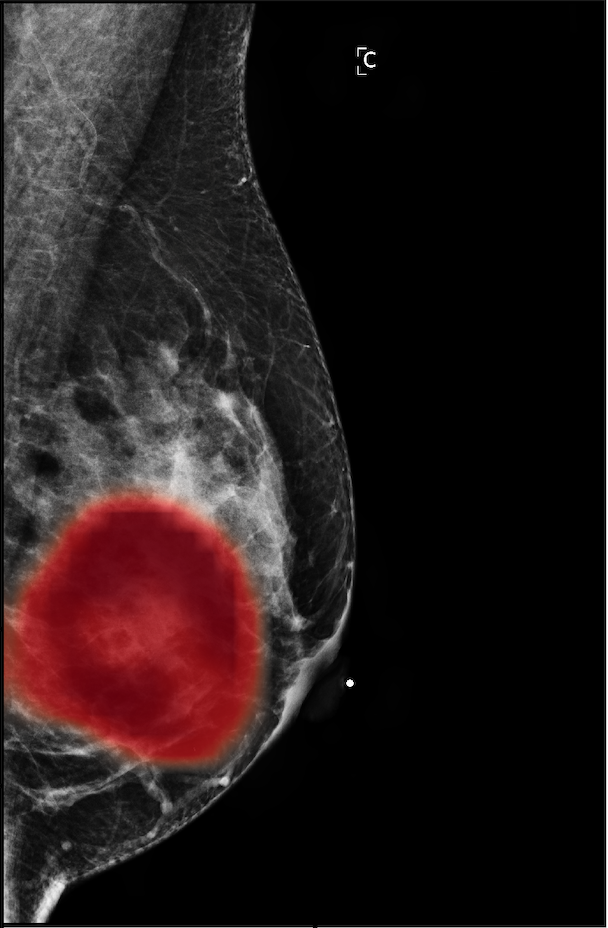

In Figure 7, we visualize saliency maps for four samples selected from the test set. In the first two examples, the saliency maps are highly activated on the annotated lesions, suggesting that our model is able to detect suspicious lesions without pixel-level supervision. Moreover, the attention is highly concentrated on ROI patches that overlap with the annotated lesions. In the third example, the saliency map for benign findings identifies three abnormalities. Although only the top abnormality was escalated for biopsy and hence annotated by radiologists, the radiologist’s report confirms that the two non-biopsied findings have a high probability of benignity and a low probability of malignancy. In the fourth example, we illustrate a case when there is some level of disagreement between our model and the annotation in the dataset. The malignancy saliency map only highlights part of a large malignant lesion with segmental coarse heterogeneous calcifications. This behavior is related to the design of : a fixed pooling threshold cannot be optimal for all sizes of ROI. The impact of is further studied in 3.6. This example also illustrates that while human experts are asked to annotate the entire lesion, CNNs tend to emphasize only the most informative regions. While no benign lesion is present, the benign saliency map still highlights regions similar to that in the malignancy saliency map, but with a lower probability than the malignancy saliency map. In fact, calcifications with this morphology and distribution can also result from benign pathophysiology [42].